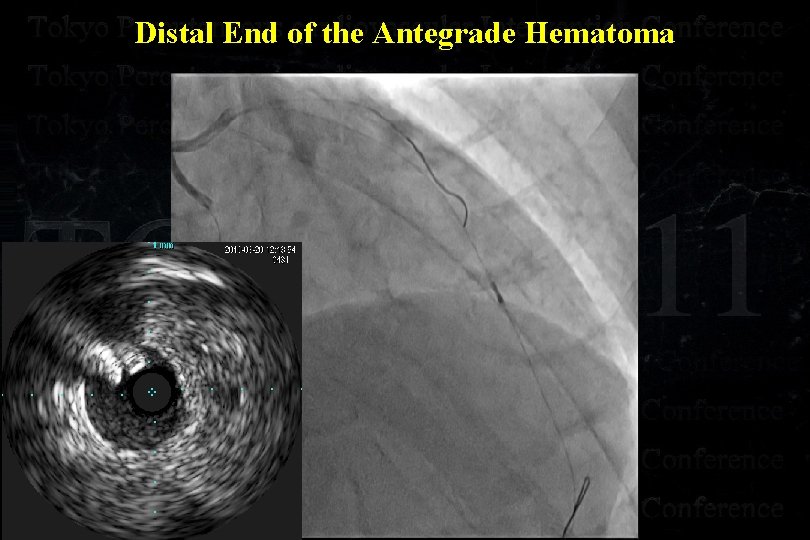

Distal End of the Antegrade Hematoma